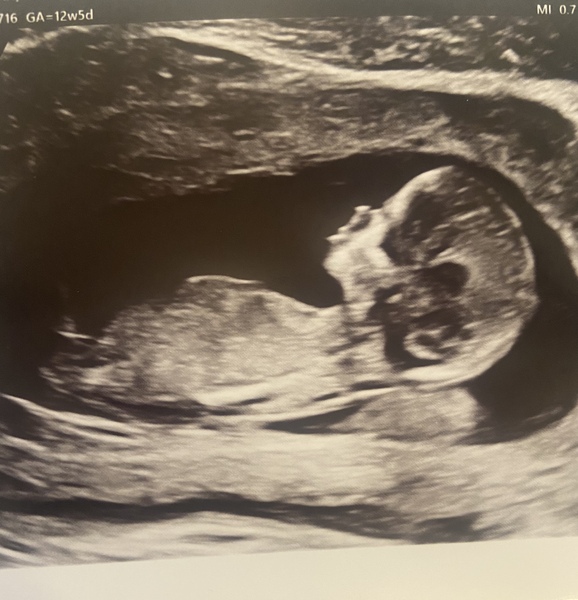

Just had my 12 week scan and baby is measuring ahead! Due date was 4th August but now moved to the 30th July!

Baby was very chilled to start with and was asleep, but after some star jumps and hip wiggles, they woke up so they could take proper measurements.

Feeling so relieved as I had convinced myself something had gone wrong!

I think it will be a big baby as they’re measuring 6 days ahead 😟! Husband and I are both convinced it’s a boy too and they asked if we wanted to know, but holding out until the 20 week scan!

What a beautiful scan! I think the few dates here and there don’t make much of a difference, I read that ultrasounds can be bad at picking that up and they compare against averages. We are also measuring about 4 days ahead and given we were trying actively to conceive, I know exactly when I ovulated. It’s a bit confusing but should be fine!

Wow what a lovely scan picture! Their little face is so clear 🥰 were they able to tell the sex today? That’s amazing if they could see that this early! Or were they just asking if you are going to find out in general?

Gorgeous scan. The clearest I've ever seen! I'd say boy too.

@Firsttimetrier what a lovely scan photo!

I’m going to be controversial and say I think it’s a girl based on the nub theory! 🥰